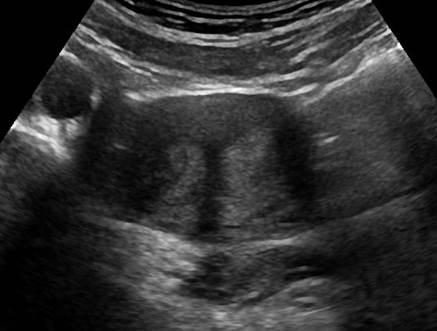

Dị dạng tử cung

Dị dạng tử cung - Ảnh 5

» Thông tin: Nữ giới – 14 tuổi.

» Lâm sàng: Kiểm tra sức khỏe.

# Tử cung có vách ngăn (Septate uterus).